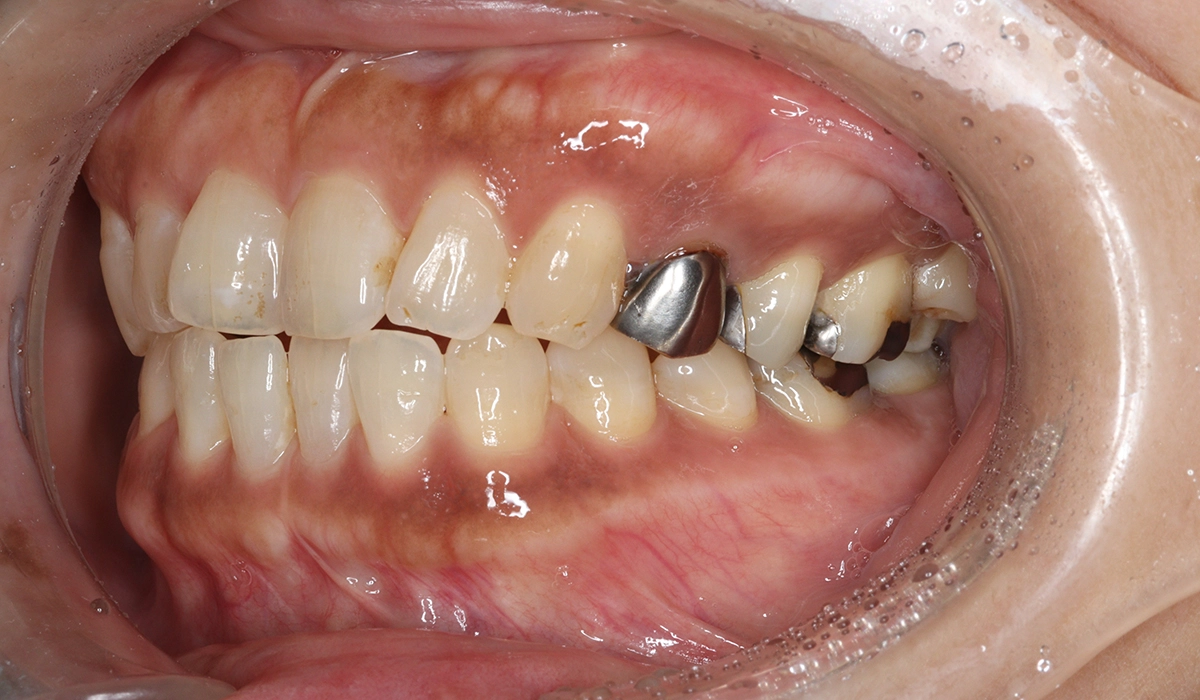

術前:左側